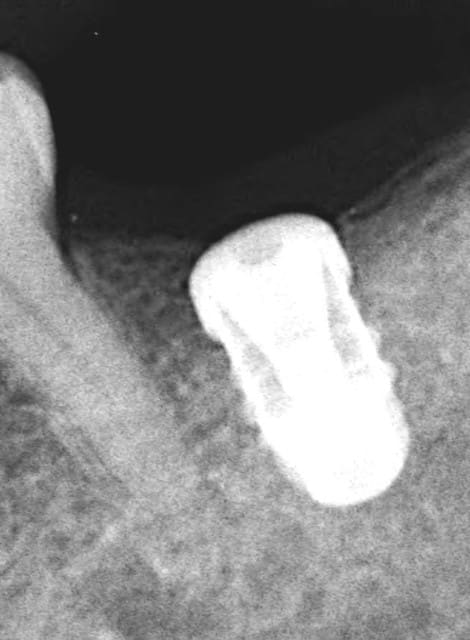

Je l'ai utilisé il y a 5 ans sur une canine en potection totale (Pas le choix car en classe 2- 2).Depuis c'est la PM derrière qui a laché. Je te joins la RX.

--

Rx implant cad 2 cpyqbp - Eugenol